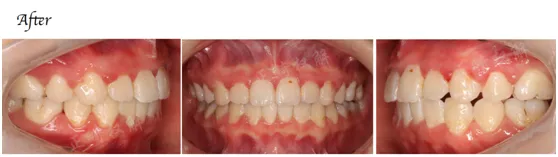

3、不拔牙病例十五例具体病例详细分析(病例从简单到复杂)(理论)

7、十五例拔牙病例分步详解(理论)